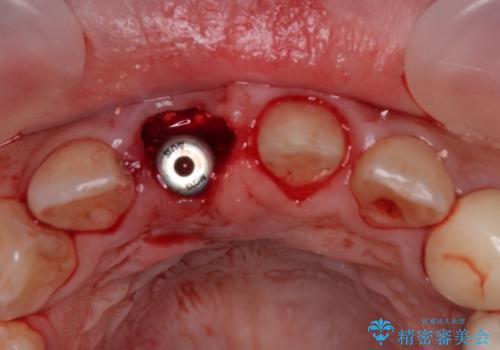

▶右上中切歯

抜歯後、即時インプラント埋入

審美性を考慮し、仮歯を即日装着

治療期間を最小限に抑えつつ、自然な前歯のラインと歯ぐきの形を維持